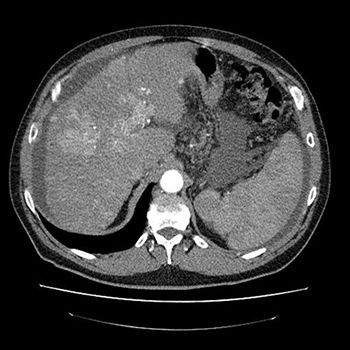

КТ селезёнки — инструментальный диагностический метод исследования, направленный на визуализацию органа с целью его изучения и выявления патологий. Он сочетает в себе рентгеновское сканирование с последующей обработкой изображений специализированным ПО. В процессе получается серия послойных снимков с шагом менее одного миллиметра.

Компьютерную томографию селезёнки, как правило, проводят в рамках комплексного исследования внутренних органов брюшины. Изолированно её назначают крайне редко — если имеются показания. Процедура требует применения контрастных веществ, которые позволяют выделить селезёнку среди других органов. Также они дают возможность выявить заболевания сосудов и опухоли добро- или злокачественной природы.

Данный вид диагностического исследования очень информативен. На КТ можно определить размеры селезёнки и их соответствие норме, выявить аномалии функционирования и развития, определить состояние стенок кровеносных сосудов, выявить патологические состояния на любых стадиях развития.